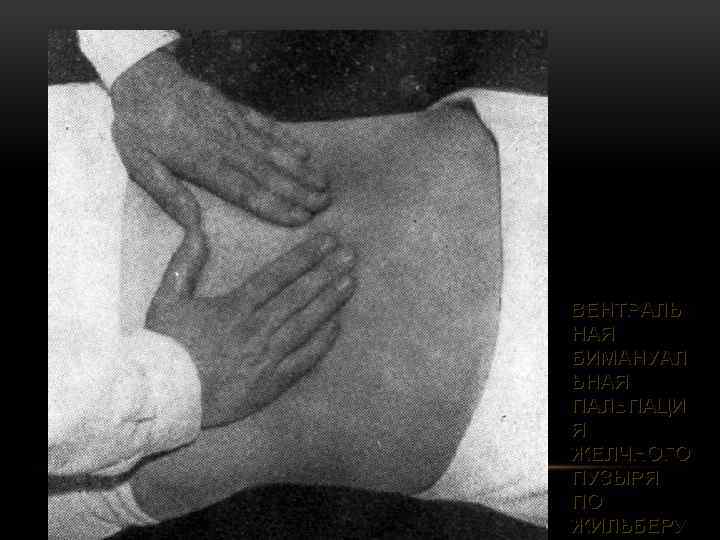

ВЕНТРАЛЬ НАЯ БИМАНУАЛ ЬНАЯ ПАЛЬПАЦИ Я ЖЕЛЧНОГО ПУЗЫРЯ ПО ЖИЛЬБЕРУ

ВЕНТРАЛЬ НАЯ БИМАНУАЛ ЬНАЯ ПАЛЬПАЦИ Я ЖЕЛЧНОГО ПУЗЫРЯ ПО ЖИЛЬБЕРУ